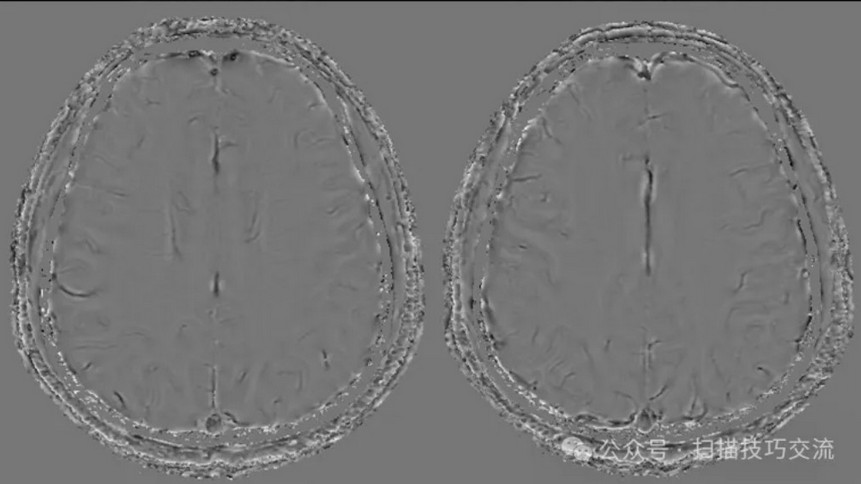

•汗腺分泌:正常,皮肤划痕正常反应。 •尿便障碍:无。性功能障碍无。 •专科情况:正常。不逐一罗列。 •辅助检查:01-05颅脑CT提示:1,上矢状窦、双侧横窦密度较高,请结合临床,必要时进一步检查;2,双侧脑室后角可疑稍高密度影,右顶叶局部脑沟密度可疑增高,建议进一步检查。 •初步诊断:静脉窦血栓

临床申请:颅脑平扫,静脉成像,磁敏感成像,颅内静脉血管黑血成像。

SWAN未见异常。